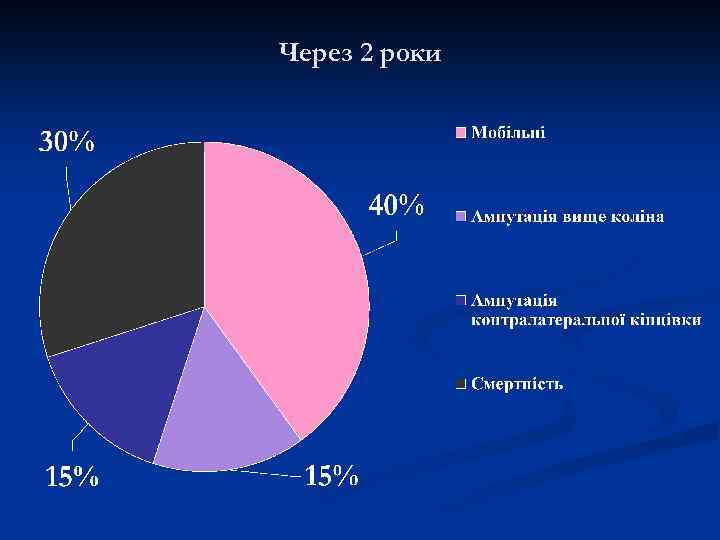

Через 2 роки

Через 2 роки